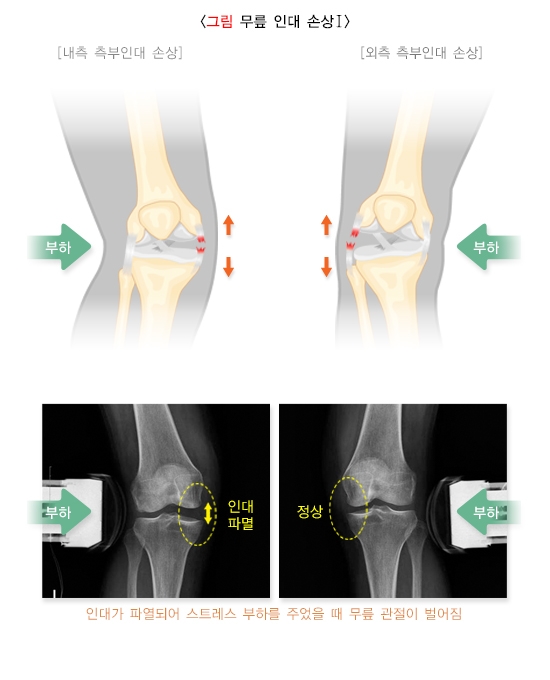

2) 관절 외부에 힘을 가하여 불안정성을 평가하는 스트레스 부하 검사는 부분 손상일 경우 오히려 손상을 악화시킬 수 있기 때문에 신중하게 시행하게 됩니다.

방사선 검사는 뼈와 관절 질환 및 연부조직(물렁조직)의 이상을 진단하기 위하여 널리 이용되고 있습니다. X선을 이용한 단순 방사선 검사와 CT, MRI 등이 있으며, 경우에 따라 손상된 인대 외부에 힘을 가하여 스트레스 부하 방사선 검사를 시행하기도 합니다.

1) 단순 방사선 검사: 신체검사와 마찬가지로, 초기에 시행할 때는 정상측과 비교하여 평가합니다. 골절의 여부를 판단하고 연부조직 손상을 가늠할 수 있습니다. 직접적으로 손상된 구조물인 인대가 단순 방사선 검사에서 보이지는 않지만, 해당 관절의 상태를 보고 인대 손상의 정도를 간접적으로 파악할 수 있습니다. 급성 손상의 경우 스트레스 부하 방사선 검사를 시행하는 것은 추가 손상의 가능성이 있으므로 신중하게 판단하게 됩니다.